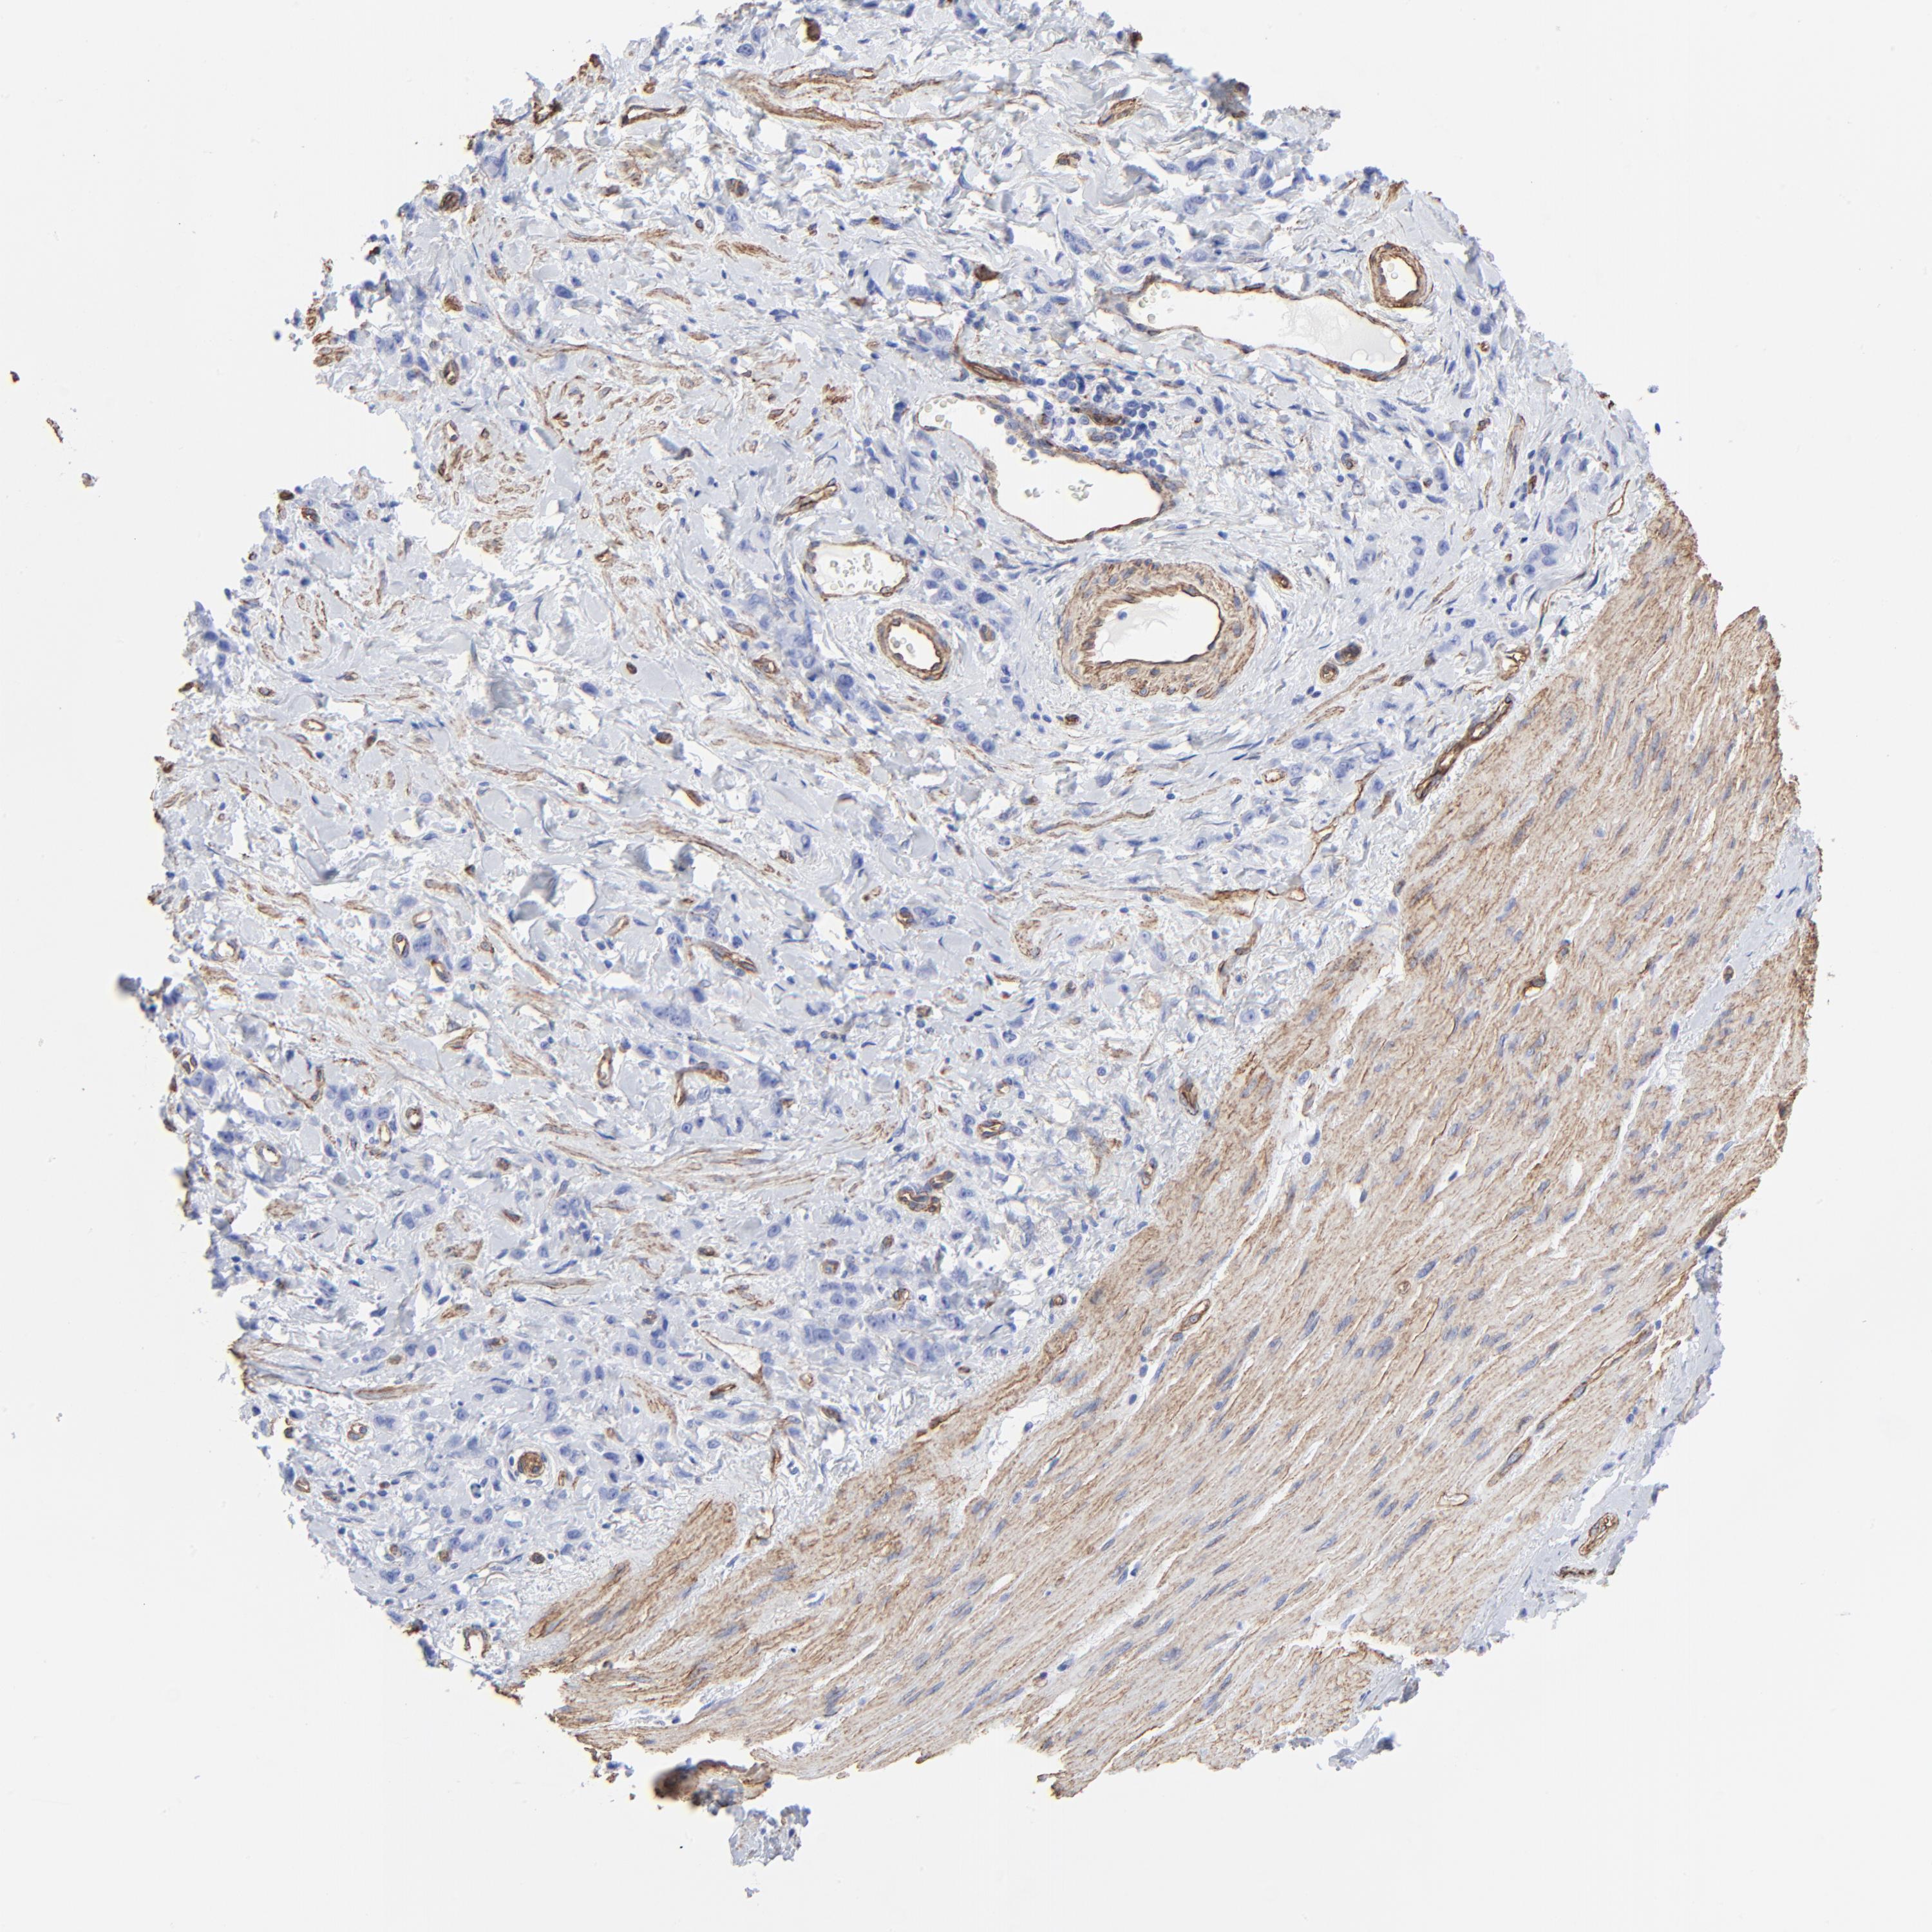

STOMACH CANCER - Protein expressioni

A mouse-over function shows sample information and annotation data. Click on an image to view it in a full screen mode. Samples can be filtered based on level of antibody staining by selecting one or several of the following categories: high, medium, low and not detected. The assay and annotation is described here.

Note that samples used for immunohistochemistry by the Human Protein Atlas do not correspond to samples in the TCGA dataset.

Antibody stainingi

Antibody staining in the annotated cell types in the current human tissue is reported as not detected, low, medium, or high, based on conventional immunohistochemistry profiling in selected tissues. This score is based on the combination of the staining intensity and fraction of stained cells.

Each image is clickable and will lead to virtual microscopy that enables deeper exploration of all samples and also displays staining intensity scores, fraction scores and subcellular localization as well as patient and tissue information for each sample.

Antibody HPA049326

Antibody CAB003791

Staining

High

Medium

Low

Not detected

Intensity

Strong

Moderate

Weak

Negative

Quantity

>75%

75%-25%

<25%

None

Location

Nuclear

Cytoplasmic/membranous

Cytoplasmic/membranous,nuclear

Adenocarcinoma, NOS

Adenocarcinoma, High grade